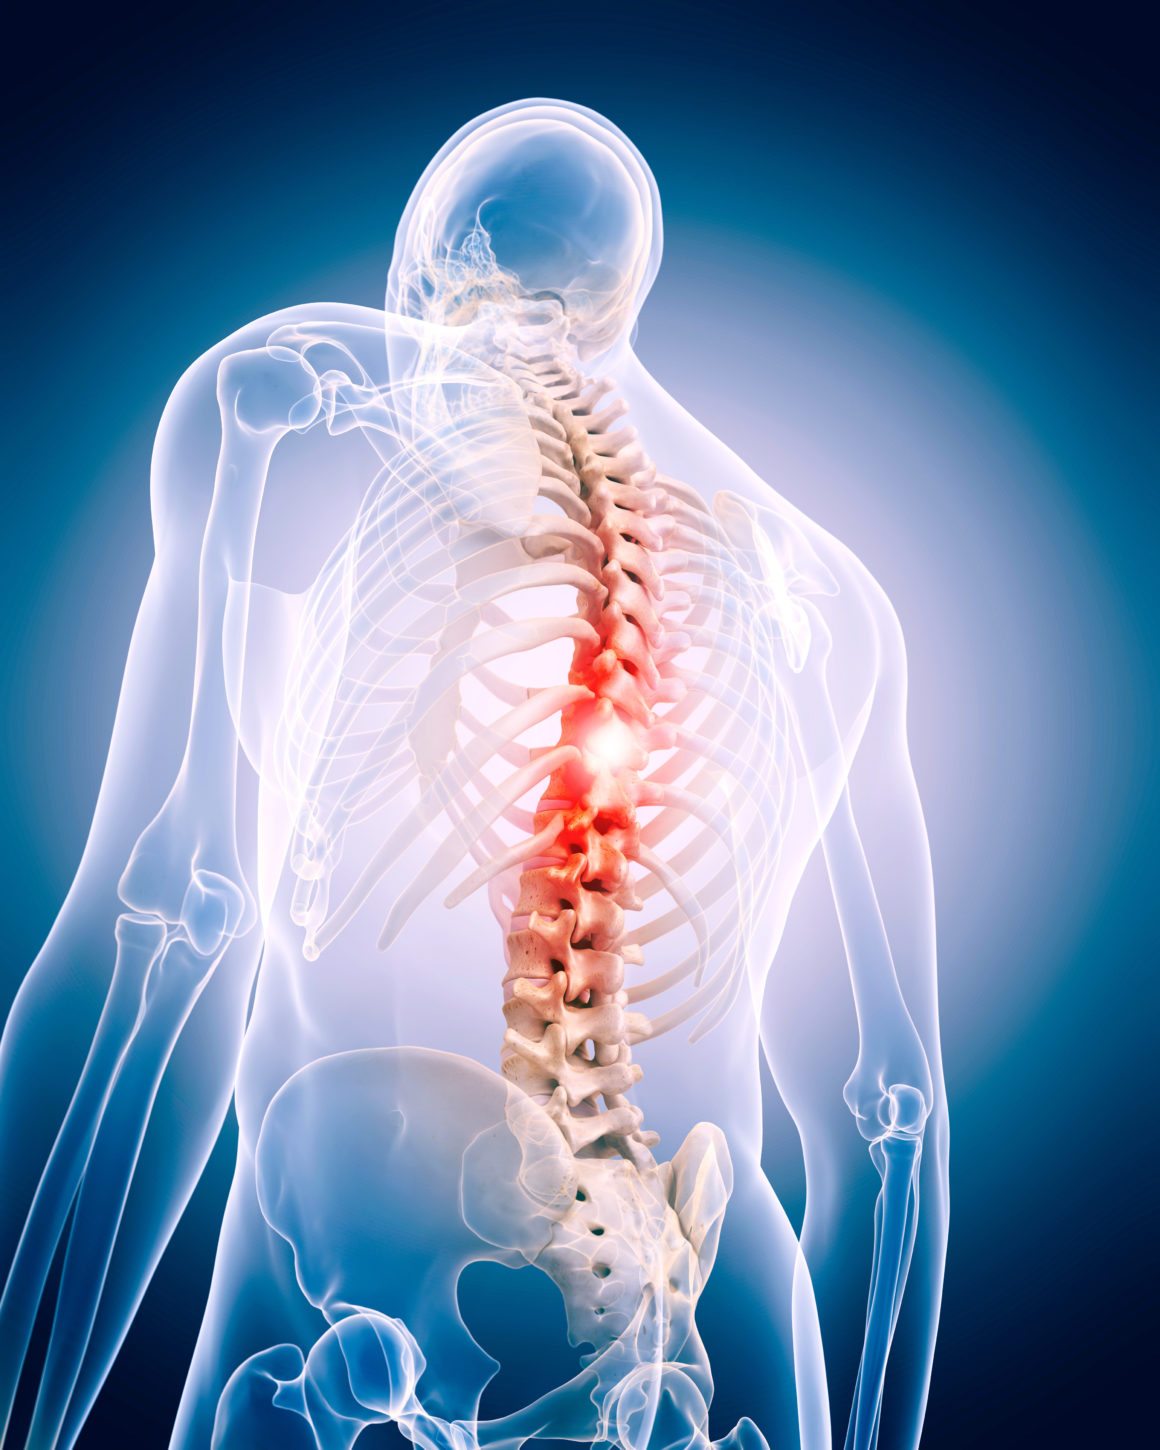

Sciatica is a common condition characterized by pain that radiates along the path of the sciatic nerve, which extends from the lower back through the hips and buttocks and down each leg. Typically, sciatica affects only one side of the body and is often associated with tingling, numbness, or muscle weakness in the affected leg. Understanding the causes, symptoms, and available treatments for sciatica is essential for managing this often-debilitating condition.

Sciatica occurs when the sciatic nerve becomes pinched or compressed. The most common causes include:

The primary symptom of sciatica is pain that radiates from the lower back to the buttock and down the back of the leg. Other symptoms may include: